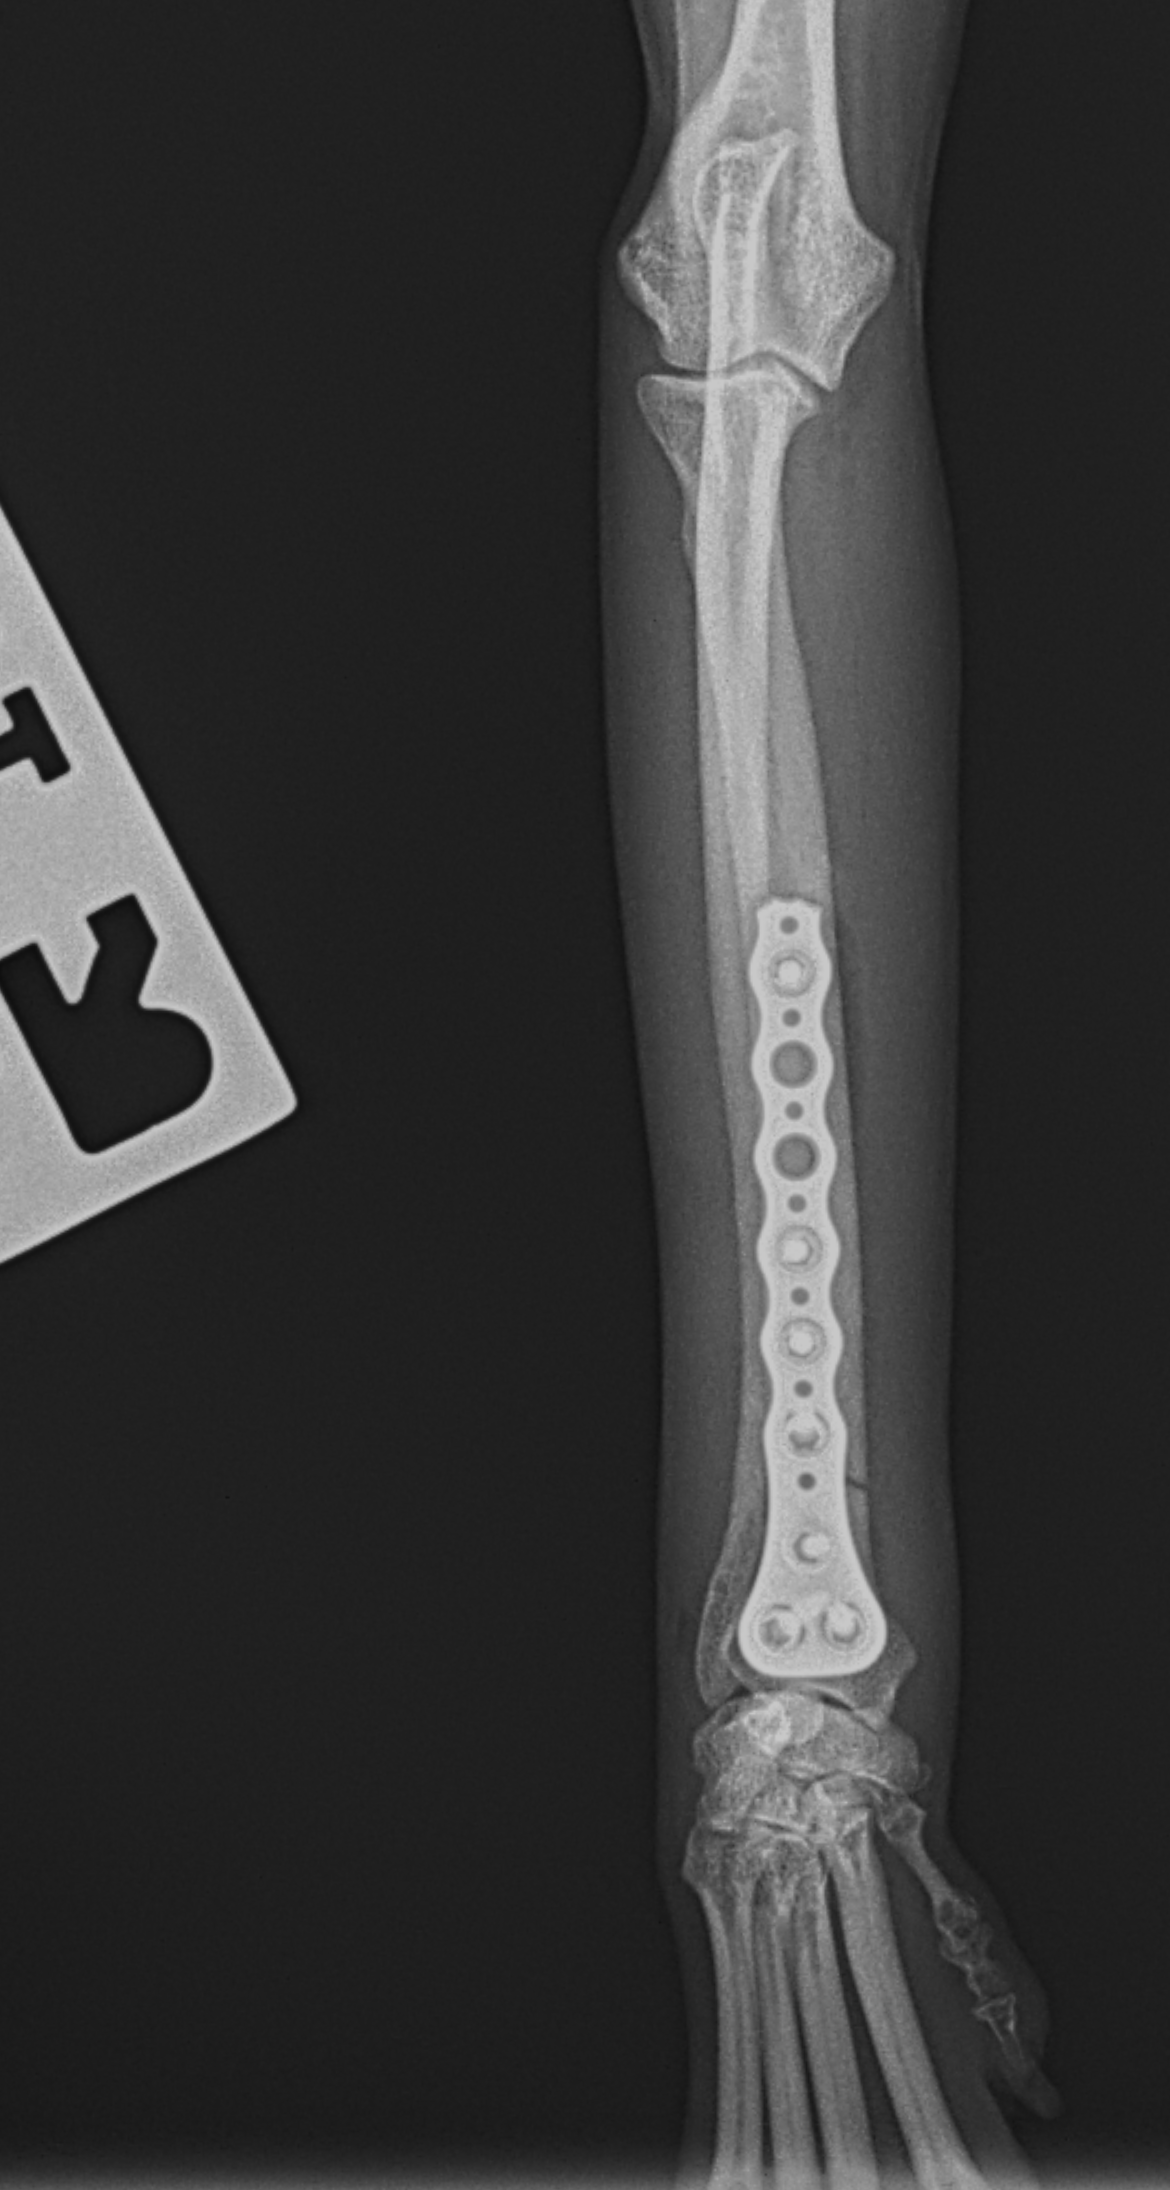

橈骨固定 #264

Toy Poodleさんが室内で転倒して骨折したとのことでかかりつけ医より整復依頼がありました。遠位端骨折です。T style Titanium Plateにコンベンショナルスクリューとロッキングスクリューを組み合わせて骨接合術を行いました。しばらくは安静が必要です。